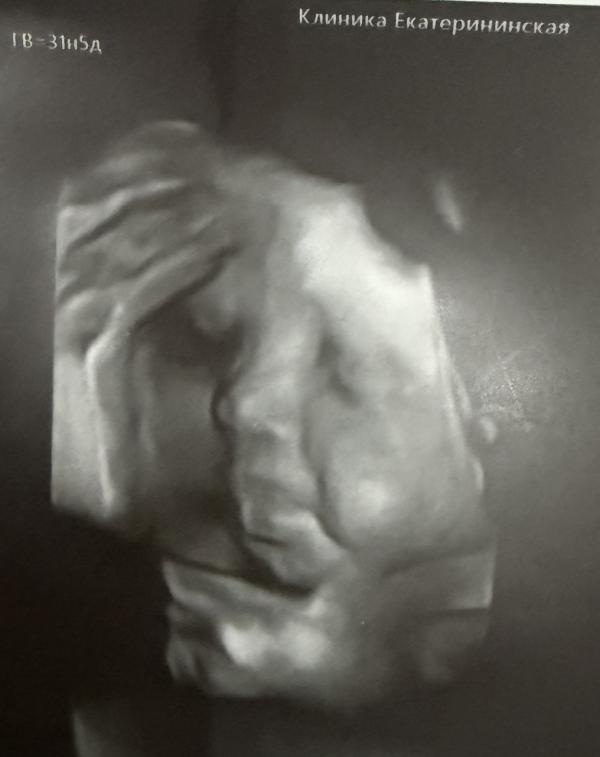

Сегодня прошел третий скрининг🥰 Малышка моя уже 1957 гр, размер соответствует сроку день в день) Умничка моя лежит головкой вниз, обвитий нет. По всей головке уже выросли волосюшки 11 мм, хотя сын и я родились лысыми😅 Теперь так не терпится посмотреть, какая она там получилась🤩 По фото губки пухлее и носик острее чем у сына) Щечки больше, но по размерам меньше сына на этом же сроке)) Шейка длинющая, аж 44 мм🤦🏻♀️ с сыном тоже такая была и родила его я ровно на 41 неделе, не хочу снова так долго ходит😭😅